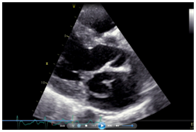

Her echocardiogram showed mild left ventricular and left atrial dilatation with normal left ventricular systolic function. The mitral valve was morphologically abnormal with the anterior mitral leaflet showing an cystic aneurysmal segment with systolic ballooning and some degree of diastolic collapse but incomplete collapse. (Figures 1-3) (Video 1) (Video 2) The aneurysmal segment showed a classical heart shape which was most evident in the end systolic frame. Colour flow imaging showed severe mitral regurgitation with an eccentric jet, the origin of the jet appeared to be through the anterior mitral leaflet. The transeosopheal echocardiography revealed similar findings (Figure 4) (Figure 5)The aortic valve was morphologically normal but for mild cuspal thickening.

Figure 3 The cystic mass appearing like a heart in the parasternal long axis view on echocardiography.

On echocardiography. Her left ventricular internal dimensions in systole/diastole were-5.3/3.2cms, her interventricular septal thickness in systole /diastole were 0.9/1.2 cms and her posterior wall thickness in systole /diastole was 0.8/1.2cms and her ejection fraction was 69%. Her anterior mitral leaflet was aneurysmal with ballooning in systole and partially collapsed in diastole and appeared like a cystic mass. Her colour Doppler showed severe mitral regurgitation and mild tricuspid regurgitation. (Her tricuspid regurgitation jet was 20mm Hg. Her aortic valve was trileaf let and normal. She had no aortic regurgitation. Her left atrium was 3.9cms and her aortic diameter was 3.1cms. Her husband also had a positive VDRL and was treated with her.

Though a cystic ‘heart shaped’ mass in relation to the mitral leaflets may be considered pathognomonic for blood cyst of the mitral valve it is unusual for the blood cyst to show any change in morphology between the systolic and diastolic frames.10 In our patient the mass definitely collapsed in diastole. However a partially endothelialised blood cyst can also collapse in diastole and show some degree of ballooning in systole. On careful review of the echocardiogram, the systolic ballooning of the cystic mass and the severe mitral regurgitation jet through the anterior mitral leaflet made us consider the possibility of an anterior mitral leaflet aneurysm. However a mitral valve aneurysm classically shows systolic expansion and complete diastolic collapse. Usually diastolic expansion of the mitral valve aneurysm, in the absence of aortic regurgitation indicates perforation of the aneurysm. So we postulated that our patient had an anterior mitral leaflet aneurysm with a perforation which caused the diastolic expansion and severe mitral regurgitation and with this diagnosis we subjected her to surgery.